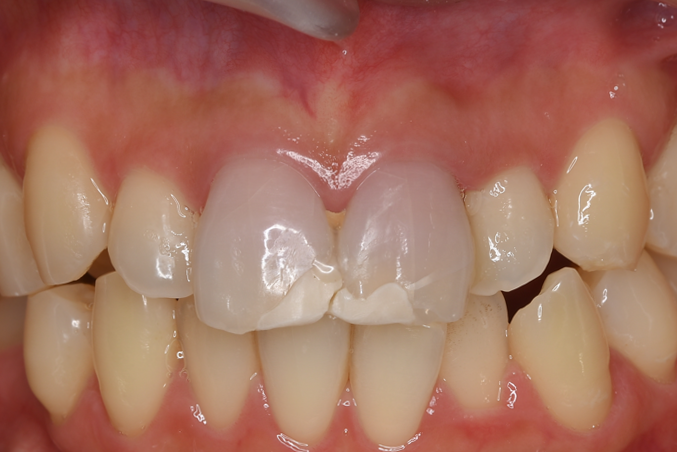

| 来院時の主訴 | 「昔、転倒して歯が欠けたところの治療したい。」 |

| 医院の診断 | 外傷による歯の亀裂、慢性根尖性歯周炎 |

| ここがこだわりのポイント!☝ | 外傷で歯の神経が壊死しており、変色歯になっていたので、丁寧に根管治療を行ってからセラミックにて審美性の回復を行なっています。 |